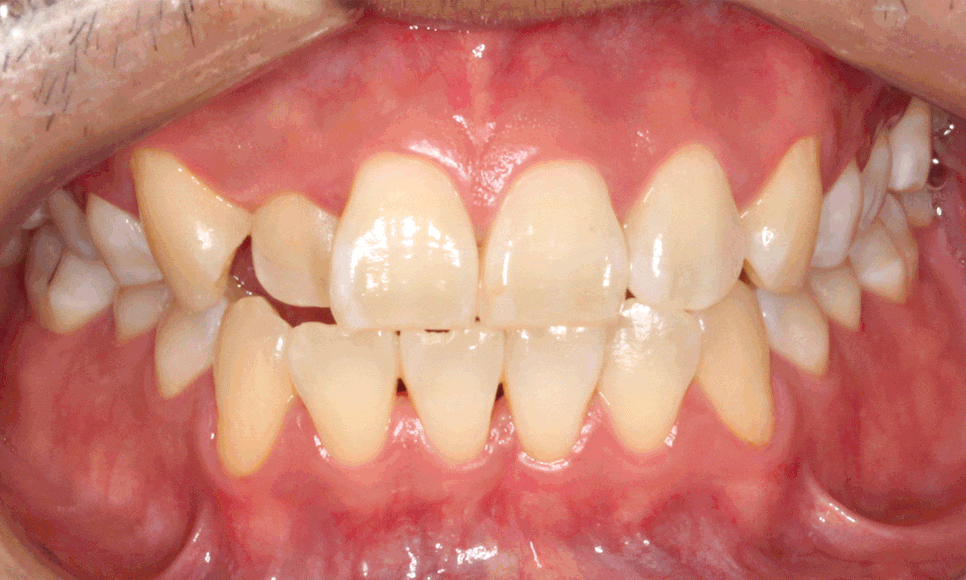

전후 사진 먼저 볼까요?

짠~

신기하죠? ㅎㅎ

배열이 처음보다 훨씬 좋아졌습니다.

잘 모르시겠다고요?

차이가 조금 더 느껴지실까요 ?^^

마찬가지로 좌 before, 우 after입니다.

이렇게 보면 훨씬 개선된 것이 눈에 띄시죠?^^

부분교정으로 진행하는 것이다 보니

전체 교정보다 완벽할 순 없지만,

환자분께서 매우 만족하셨습니다.

가장 신경 쓰여하셨던 #12 치아가

앞으로 나오면서 훨씬 가지런해지고

아래 치아 치축도 개선되면서

더욱 정돈된 이미지를 가지셔서

크게 만족하셨습니다.